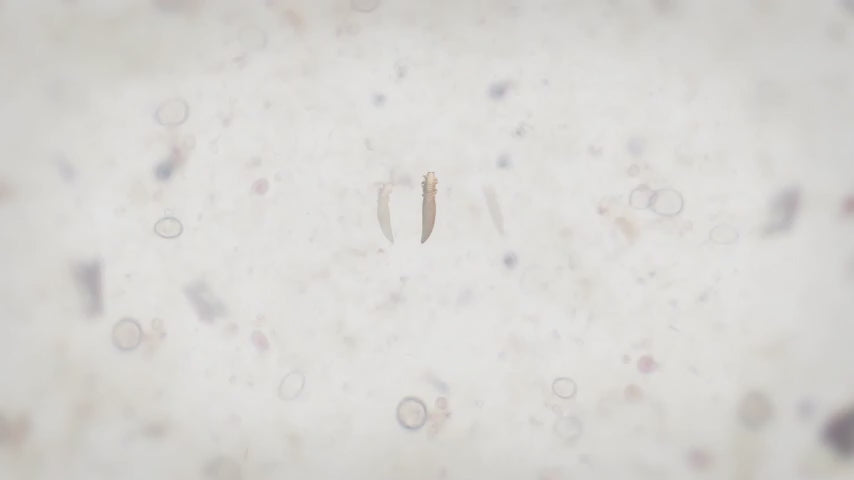

Every day, your eyelids collect a disgusting mix of bacteria, dead skin cells, oil, makeup residue, and tiny mites called Demodex.

These mites literally live on your lash line and feed on the oil in your glands. Over time, all this buildup clogs your meibomian glands, the tiny oil glands in your eyelids that are supposed to keep your tears from evaporating too fast.

When those glands get blocked, your tears dry up in seconds. And that's when the burning, redness, and irritation start. The Blinkjoy system works in two simple steps.

First, you apply the HOCl Gel Cleanser to the Electric Eyelid Brush. Hypochlorous Acid is a powerful antimicrobial agent that kills bacteria and Demodex mites on contact, it's the same stuff your immune system makes to fight infections.